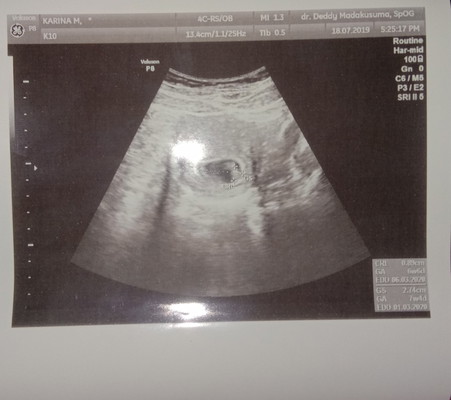

Bun ada yang bisa baca usg gak? Itu di pojok kanan bawah kan ada usia nya brpa week yg bener yg atas apa bawah ya soal nya kana ada dua tuh

Yang atas itu usia janin dan hari perkiraan lahir sesuai deteksi alat USG. Yang bawah itu usia janin dan hari perkiraan lahir sesuai perhitungan HPHT (hari pertama haid terakhir), hitungan HPHT sudah peraturan internasional seperti itu. Tidak perlu khawatir.. bedanya tidak jauh. Berarti bunda melahirkan nanti normalnya diantara tanggal itu. Tgl 1-6 Mei. Terkecuali SC sebelum tanggal itu. Sebab sudah dijadwalkan oleh dokter.

Baca lagiGA itu gestational age/perkiraan usia kandungannya.. GS itu gestational sac/perkiraan ukuran kandungan.. Jd klo atas itu usia kandungan sesuai ukuran janin klo gk salah bun, klo yg bawah itu usia kehamilan sesuai ukuran kantung hamilnya gitu klo dulu q d jelasin deh.. klo gk salah lho ya tapi takut lupa q nya hehe

GA itu usia kehamilan bun...7 minggu 4 hari Klo yg di bawahnya lagi itu tanggal HPL bunda๐

Yang bawah GA 7w4d bun

6w 6d